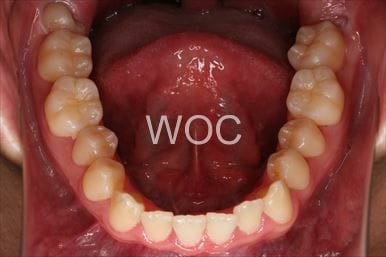

治療前3

治療前4

治療前5

- 年齢:20歳女性

- 主訴:出っ歯が気になる

- 基本矯正料金:120万円

- 治療期間:1年7ヶ月

- 抜歯部位:上顎両側第一小臼歯